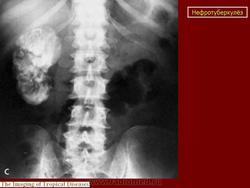

Рентгенологические методы исследования: флюорография (рентгенография) легких, обзорная и внутривенная урография в различных модификациях, томография почек, ретроградная пиелография, цистография, уретроцистопростатография, ангиография и др. Обзорный снимок мочевых путей позволяет обнаружить обызвествления в органах мочеполовой и других систем, изменения опорно-двигательного аппарата (туберкулезный спондилит, метастазы при раке почки и т. п.), определить контуры и размеры почек (увеличение или уменьшение, выбухания, втяжения). По внутривенной урограмме оцениваются функциональное состояние почек и анатомические особенности чашечно-лоханочной системы, мочеточников, мочевого пузыря; урография - основной рентгенологический метод исследования. Соответственно форме и стадии нефротуберкулеза могут быть выявлены; при субклиническом нефротуберкулезе - слабое контрастирование чашечно-лоханочной системы, хаотичное расположение чашечек, их деформация, при папиллите («начальном» деструктивном нефротуберкулезе) - неровность, стушеванность, нечеткость контуров чашечки ввиду наличия признака деструкции, при кавернозном туберкулезе - наличие полостей как в корковом, так и в мозговом слое с неровными, фестончатыми краями; при туберкулезном пионефрозе - изображение увеличенной почки с выбухающими неровными контурами, наличием больших полостей распада, нередко сливающихся между собой, резким снижением либо потерей функции (выключение - аутонефрэктомия); при нефросклерозе (вторично-сморщенная почка) - почка небольших размеров.

Начальный признак специфического поражения мочевых путей - расширение чашечно-лоханочной системы и мочеточника (снижение их сократительной способности в результате токсического воздействия, изменения функционального характера). Во всех случаях «неясной» уретерогидронефротической трансформации врач должен предположить наличие туберкулеза мочевой системы. В дальнейшем обнаруживают различные деформации чашечно-лоханочной системы (с уменьшением ее емкости) с явлениями гидрокаликоза; сужения мочеточника с расширением его выше стеноза; натянутость, четкообразную форму мочеточника; симптом подтянутости стенки мочевого пузыря; уменьшение емкости и различные деформации его контуров вплоть до появления двойного контура - симптома «песочных часов». При восходящей или микционной цистографии, урет-роцистопростатографии выявляют пузырно-мочеточниковый рефлюкс, а при последней - сужения уретры и затекание контрастного вещества в полости предстательной железы. Томографию почек применяют для уточнения контуров почки. Ретроградную пиелографию выполняют при неинформативности внутривенной урографии и для выяснения характера выключения туберкулезного очага (сопоставление пиело- и урографических данных). Ангиография позволяет получить представление об ангиоархитектонике пораженной почки, что важно при определении хирургической тактики.